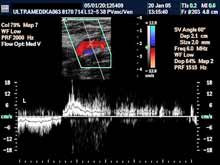

A) Krvni sudovi vrata

Vrsta i sadržaj pregleda:

- Pregled velikih krvnih sudova vrata CD i CPA

modom (obavezno karotidnih i vertebralnih arterija celim tokom).

Pregled podrazumeva procenu ukupne debljine krvnih sudova (indirektna

procena koronarne bolesti), procenu stepena suženja, karakteristika aterosklerotičnog plaka, procena hemodinamike i postavljanje

indikacija za operativno lečenje.

Primenjena tehnika:

- Sono CT,

- XRes,

- 2D Broad band,

- Broad band - CD,

- CPA ,

- CPD.